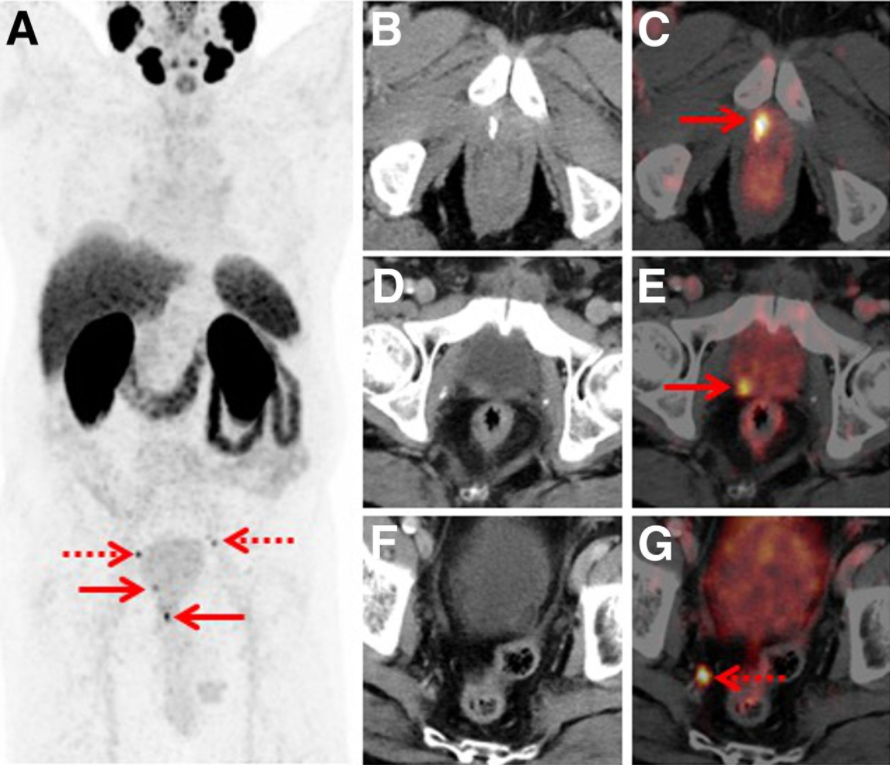

VISION研究中针对的是PSMA阳性患者(采用68G标记PSAM-11的PET扫描),目前临床上68Ga-PSMA-11 PET/CT与18F-FDG PET/CT均可用于前列腺癌的诊断和分期,这两种显像技术在疗效反应和预后判断方面有怎样的差异,本次ASCO-GU全体大会上的一项2期试验将提供参考。

VISION研究采用68Ga-PSMA-11 PET/CT扫描筛选患者

一例前列腺癌根治术后患者(PSA 0.15 ng/mL)行18F-rhPSMA-7.3 PET检查发现的盆腔细小复发病灶